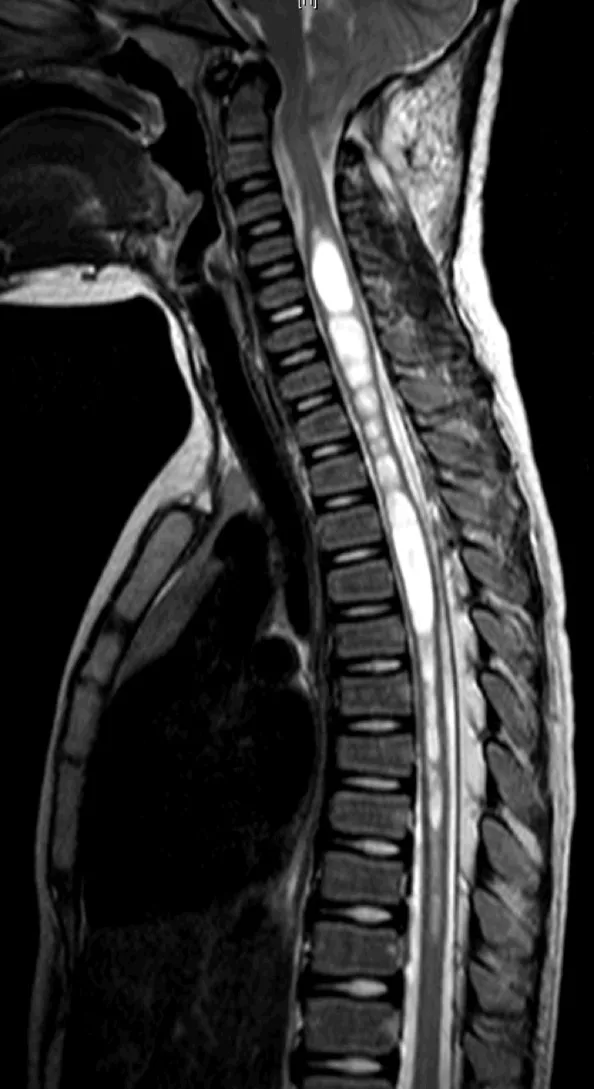

起初,医生只检查出了玮玮患有轻微的脊柱侧弯,但是,当得知孩子还出现了共济失调的症状时,医生立即建议一家人前往神经外科就诊,进行更加详细的影像检查,于是,玮玮就这样被查出了患有小脑扁桃体下疝畸形(CM,又称Chiari畸形),并伴有脊髓空洞症。

小脑扁桃体,这个在正常情况下位于颅腔内的组织,一旦向下进入颈椎管内超过枕骨大孔5mm,就成了一种危害性极高的先天性神经畸形——小脑扁桃体下疝畸形。而它通常会导致人体的脊髓变成“空心萝卜”。

这一现象被称为脊髓空洞症,是一种慢性、进行性病变。如果将脊髓看作一根实性的萝卜,正常来说中间是没有空腔的,然而脊髓空洞症会导致萝卜内出现大大小小的空洞,这些空洞内充满着液体(脑脊液),像一条条管状的“囊肿”,并随着它不断膨大,逐渐破坏周围的神经组织,从而引起一系列临床症状。

术后脊髓空洞明显改善

几天后,手术如期进行,在Rutka(鲁特卡)教授的主刀下,手术十分顺利,小脑扁桃体下疝畸形成功去除后,玮玮的脊髓空洞也明显缩小。